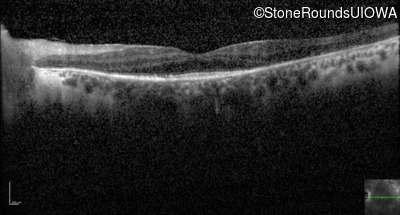

Optical Coherence Tomography - Left - 20/70 +1

Exemplar / OCT Stack